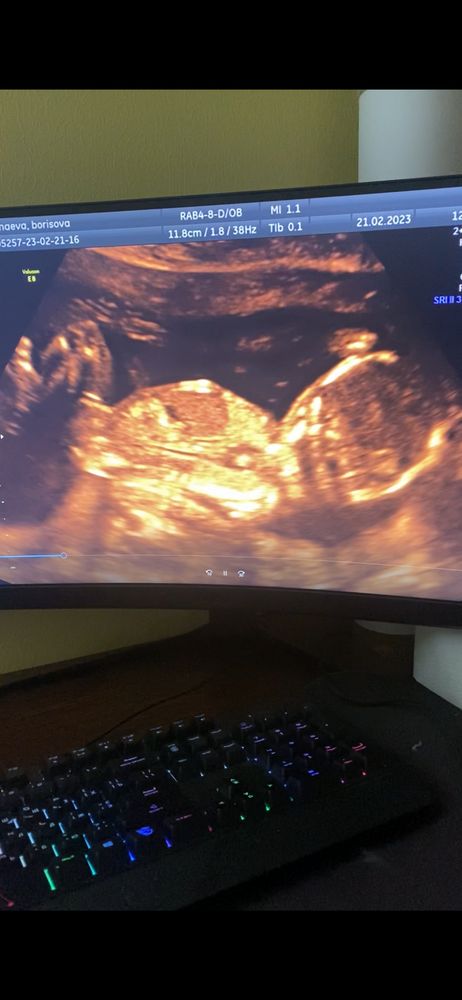

Мальчик или девочка

Мне кажется, для полового бугорка длинновато, скорее фрагмент пуповины.

Чашка утреннего кофе, половой бугорок короче должен быть? Просто так много фото выкладывают с длинными белыми полосками и и пишут, что это бугорок.

По наклону вроде на девочку смахивает

похоже на девочку

Мне кажется тут вообще не видно и не понятно что это . А что вам на узи не сказали кто?

Олюшка, в 12 недель сказали похоже на девочку, в 15 не сказали кто

Мне кажется он, и это девочка